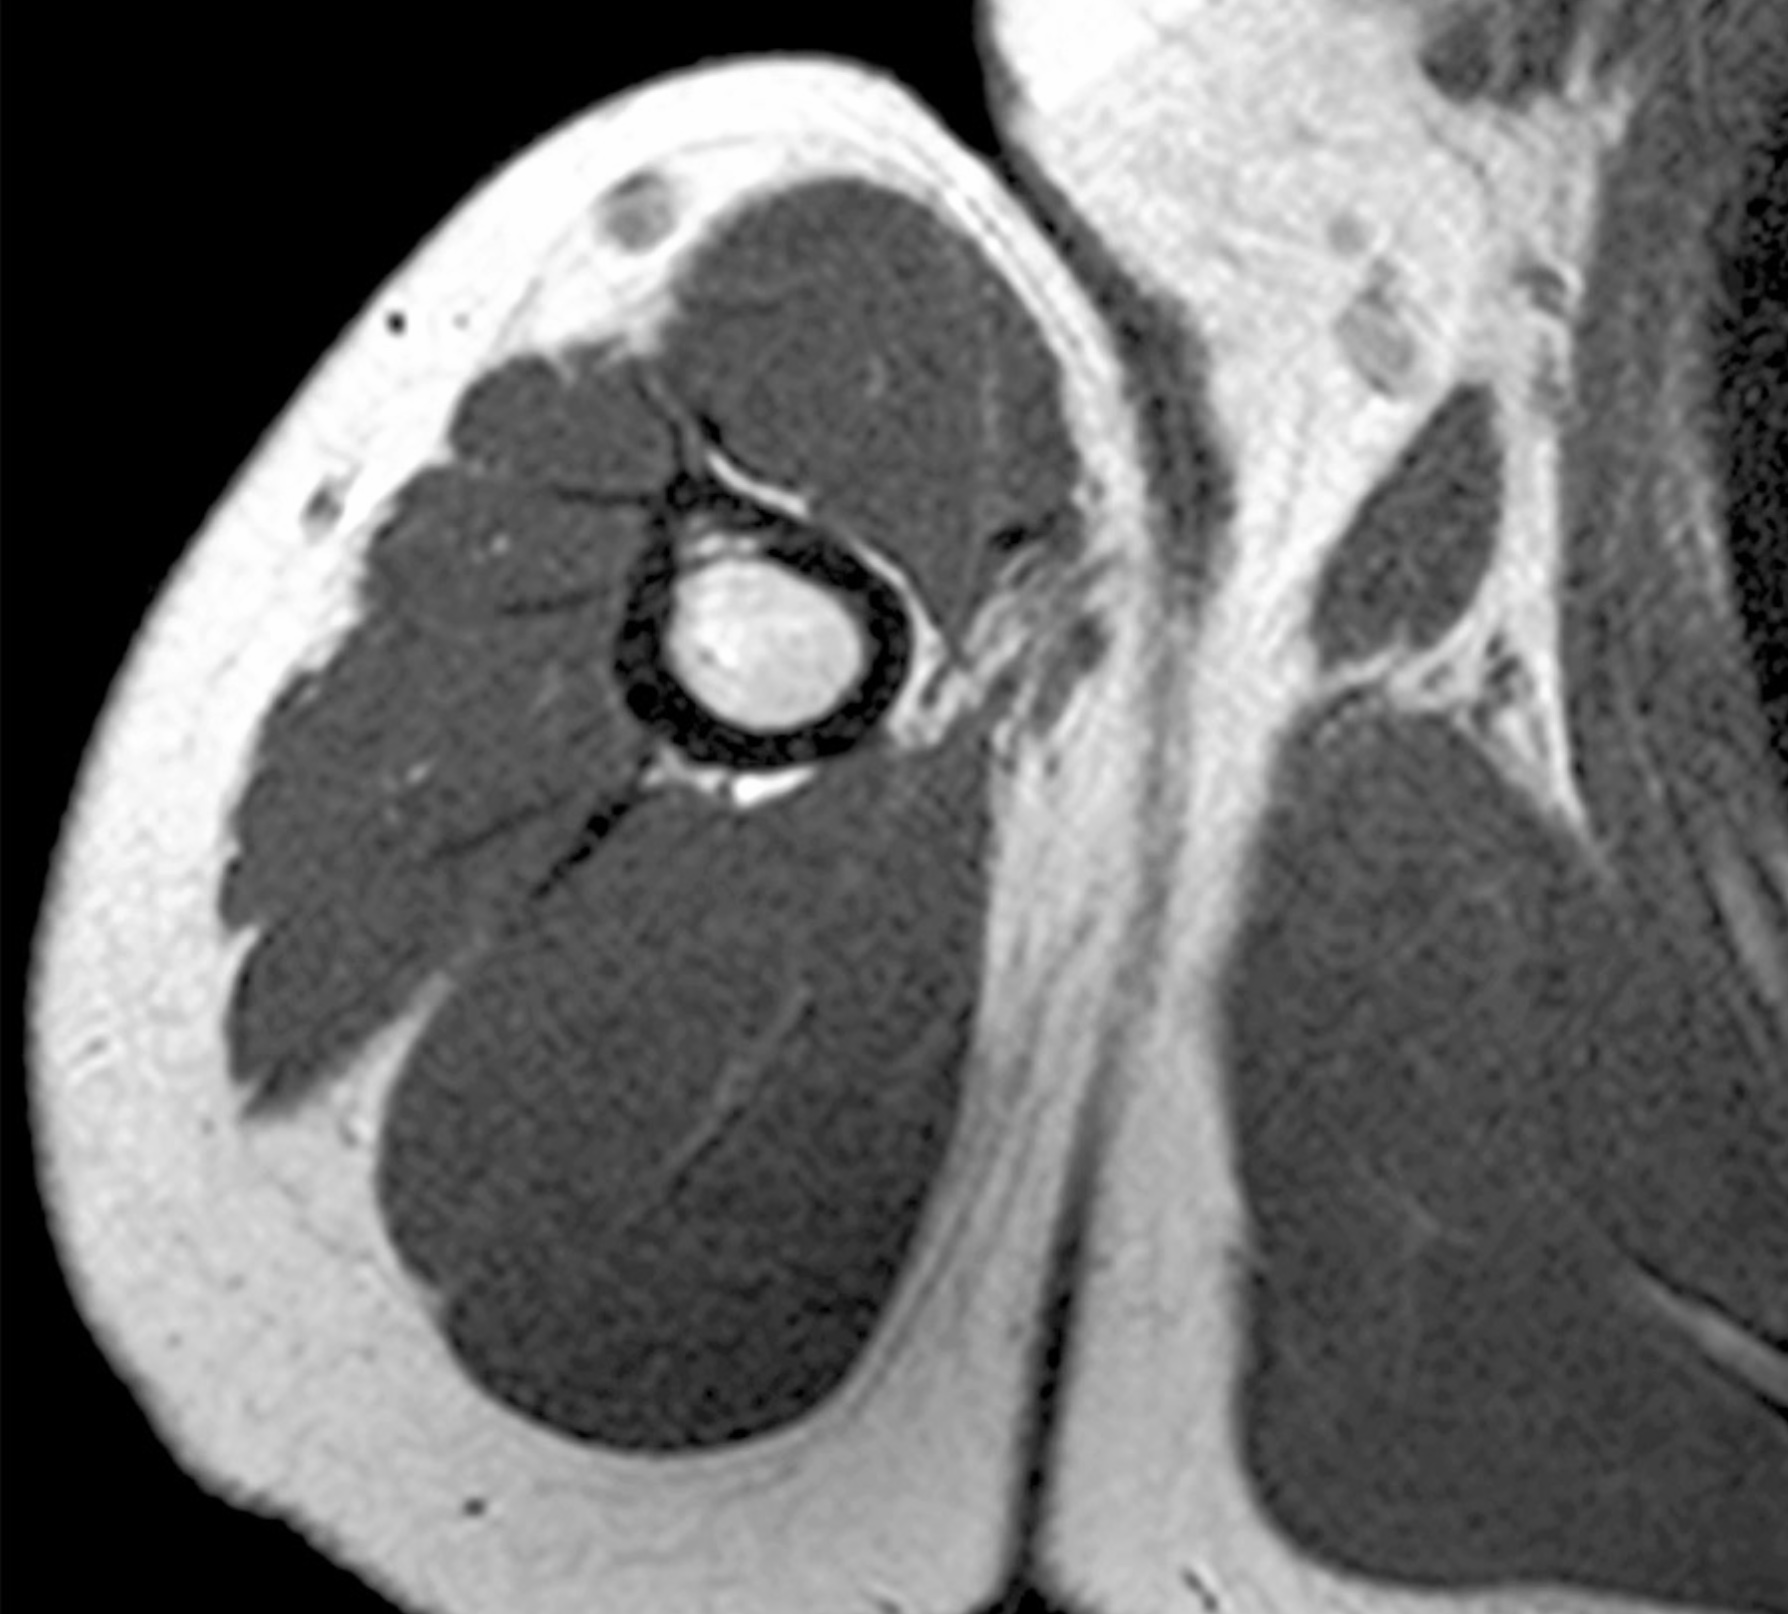

1. A patient complains of shoulder pain and difficulty rotating their arm. An ultrasound reveals edema within the spinoglenoid notch, which could explain weakness in external rotation at the glenohumeral joint. Describe the normal scapular and shoulder anastomosis, including all arterial branches involved and their relationship to any ligaments, scapula borders, and intermuscular spaces. If the axillary a. is ligated immediately distal to the thyrocervical trunk, would this edema affect active collateral circulation? (If yes, explain.) Also, include a brief (2-3 sentences) explanation for why edema within the spinoglenoid notch might result in weak external/lateral rotation of the shoulder.

2. A 29-year-old police officer receives a gunshot wound to the right shoulder. The bullet causes instability of the glenohumeral joint. Describe the supportive anatomical structures that aid to stabilize and reinforce the shoulder joint, including fibrous tissue, membranes, ligaments, muscles, innervation, function/action, and any relationships. Also, discuss the muscles that assist in upper limb abduction from 0 to 180 degrees and their range of movement.